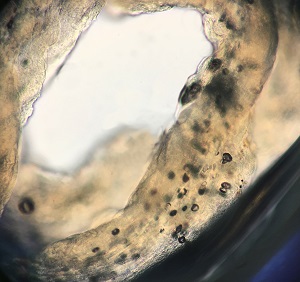

A 36-year-old male returning from a 3-month stay in rural China sought medical attention for a tender, slowly migrating nodule that had developed on his abdomen. The subcutaneous mass was excised in the clinic; a motile, ribbon-like object approximately 5 cm long was found within. The organism was placed into 10% formalin and submitted to the DPDx Team for identification. The gross morphology of the organism is shown in Figures A and B; Figure C shows the internal structure after exposure to lactophenol (100x magnification).

Figure C